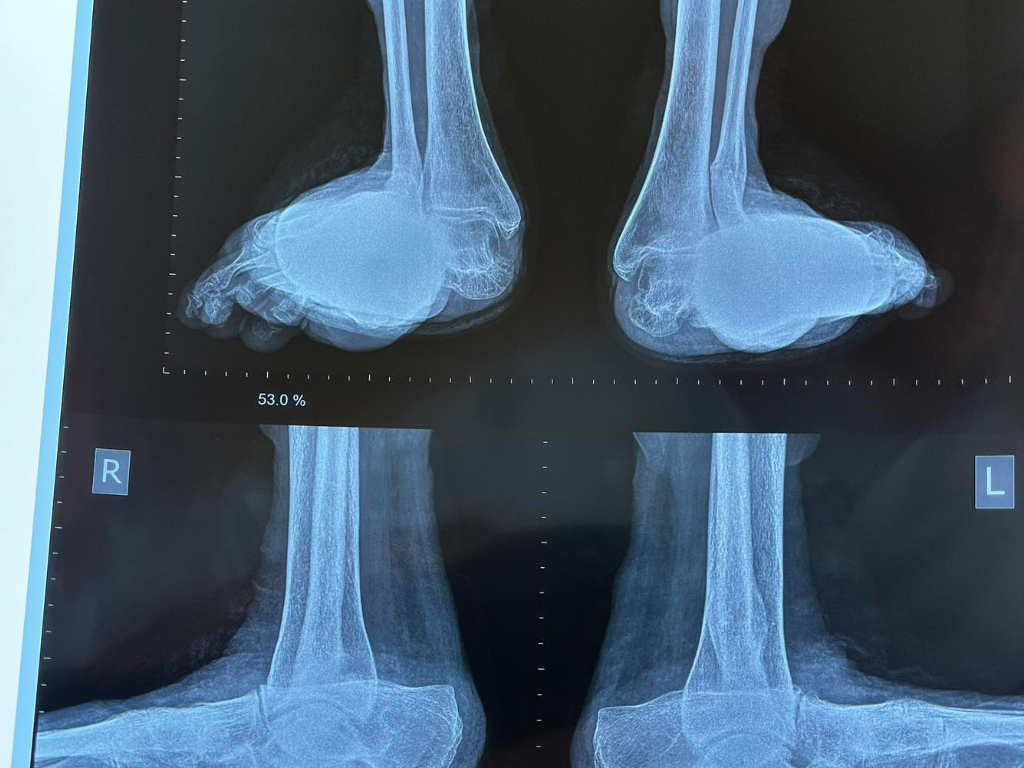

Last year we straightened up the right foot of a patient with severe deformities due to rheumatoid arthritis. Last week we gave her a matching pair. We were all delighted with the results!